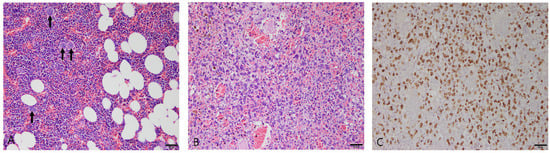

3.2.1. Nodular Hyperplasia

3.2.4. Splenic Lymphoma

3.2.5. Stromal Sarcomas